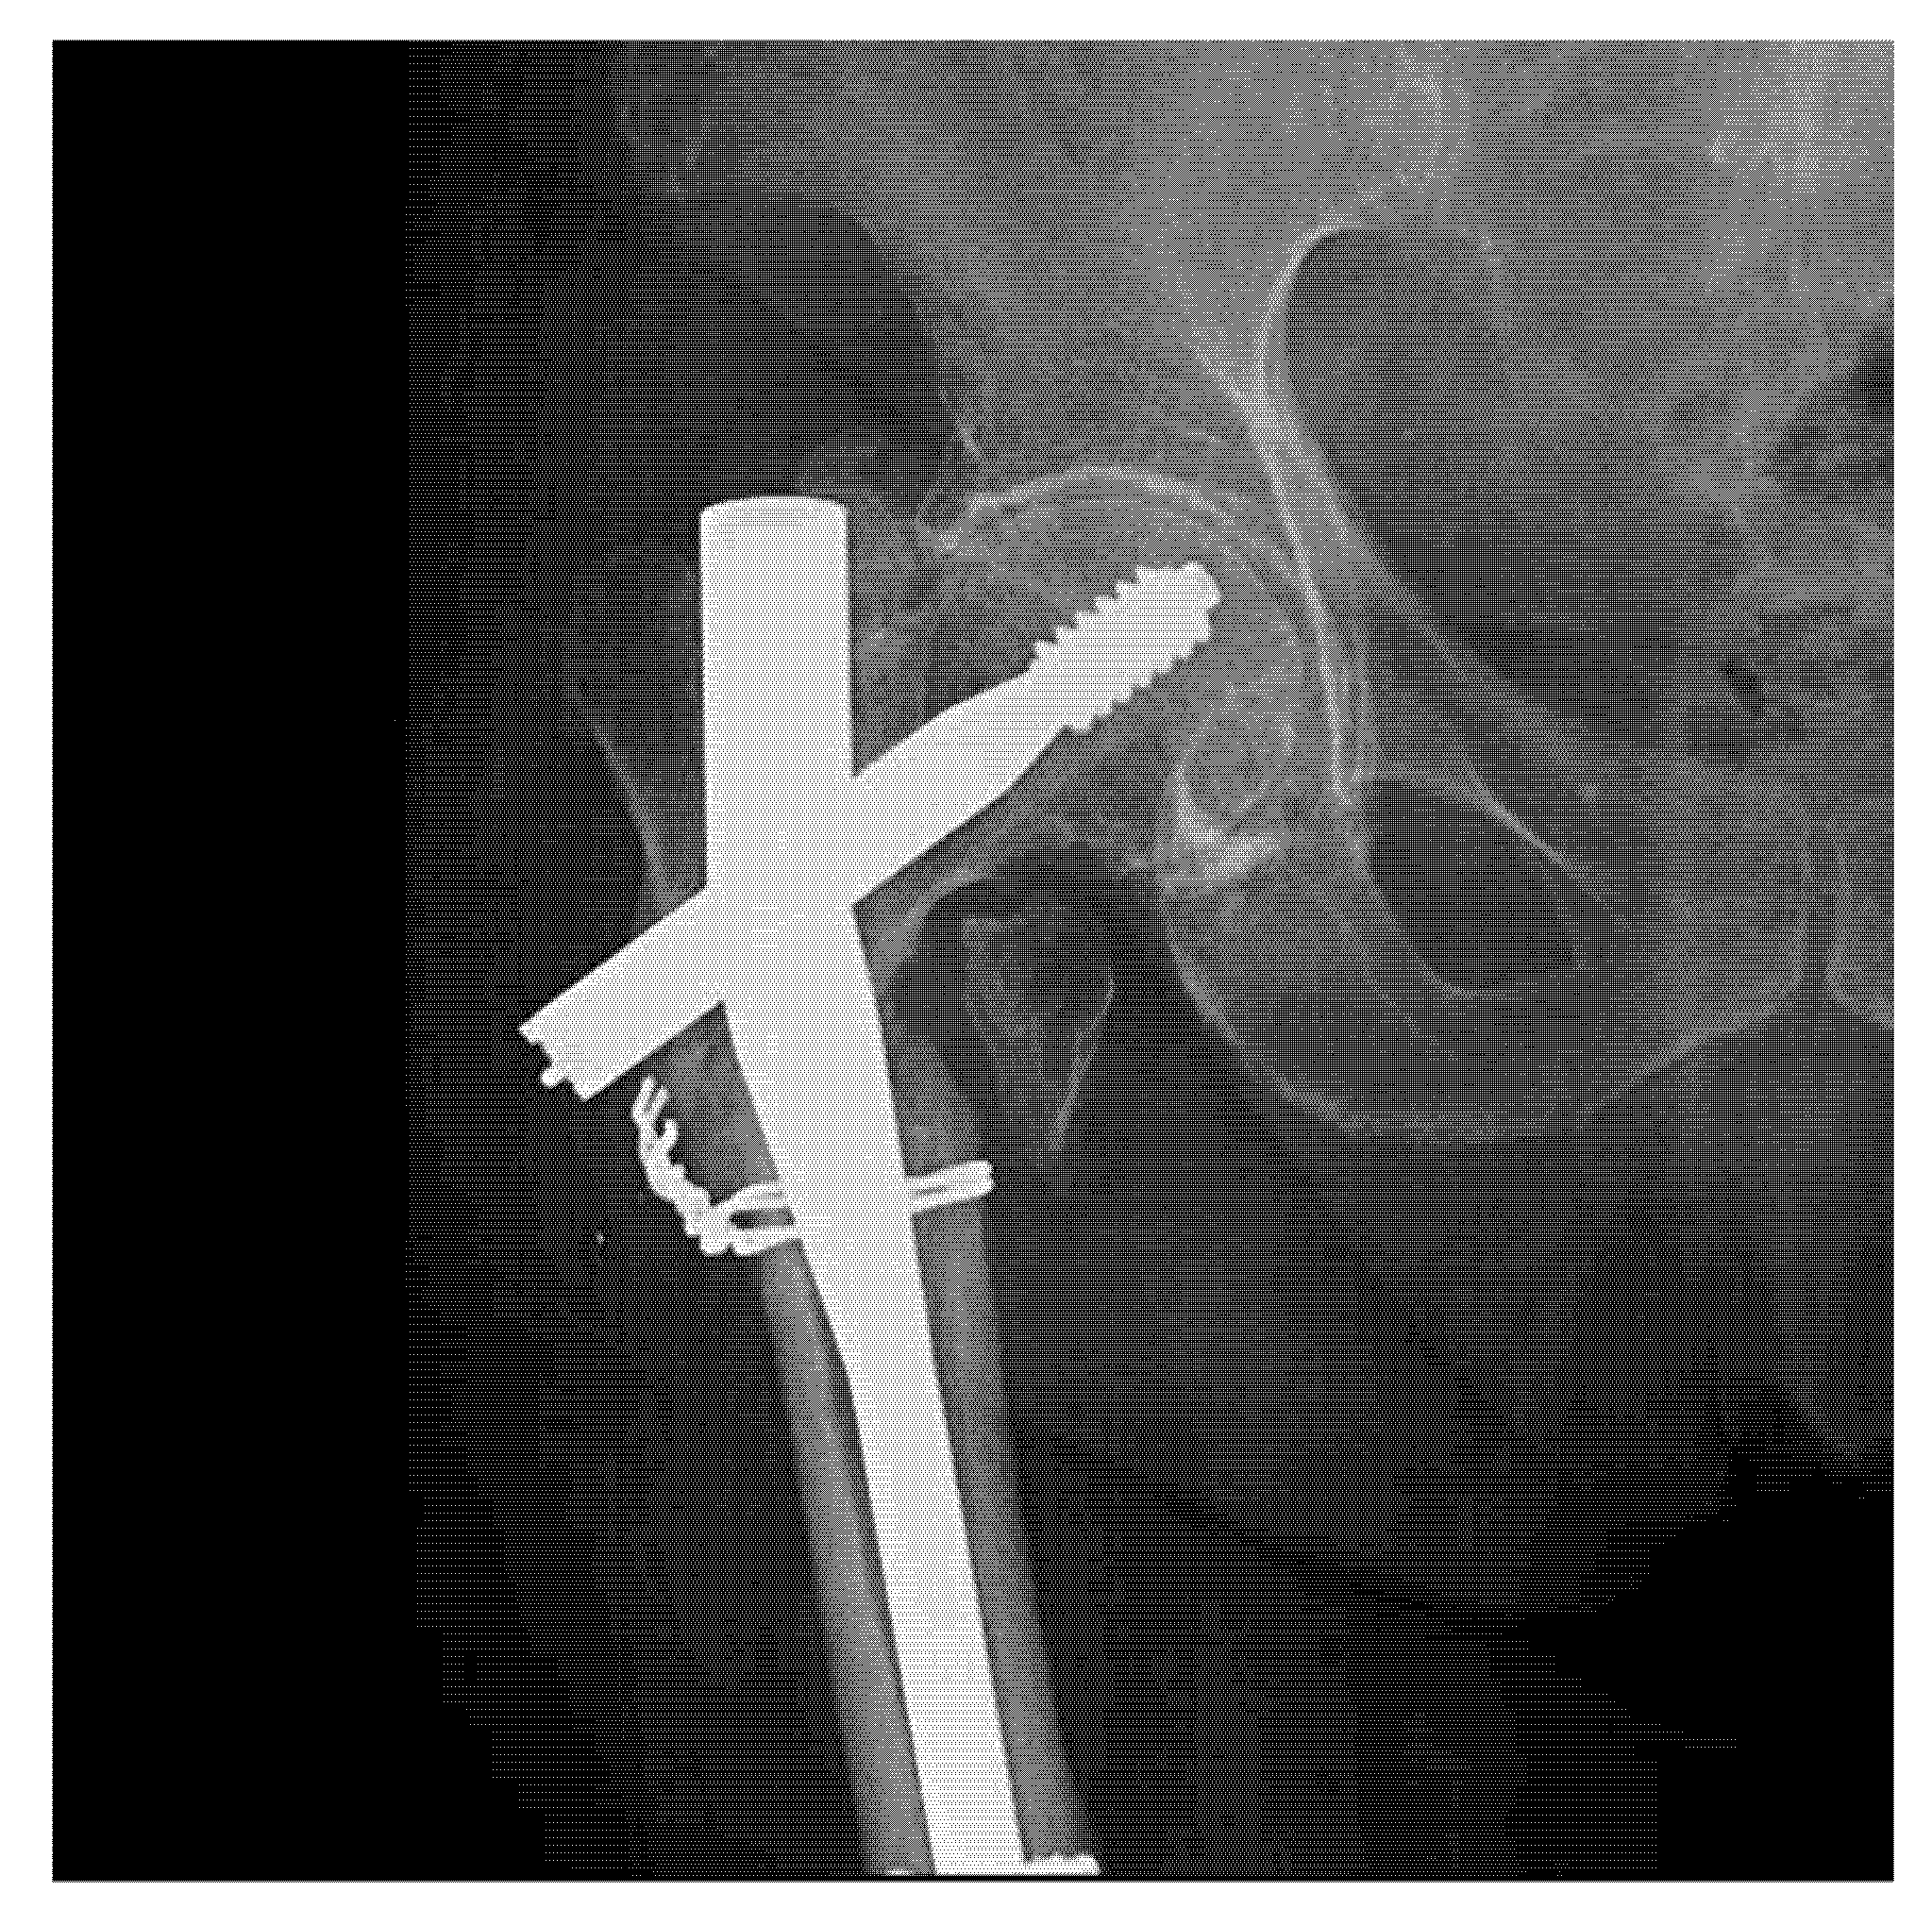

For intramedullary nails, it is well-recognized that the failure process is usually initiated in the locking holes, proximally or distally (case presented in Figure 6). Sliding screw hip plates are prone to significant wear and corrosion due to moving components [37,38]. For plates, the breakdown starting point is commonly situated around the holes where the cross-sectional area is reduced and where interaction with the screw heads generates wear and corrosion fatigue under localized stress concentration [39].

Figure 6.

Radiography of a clinical case with failure of a Gamma Nail—72-year-old female patient.